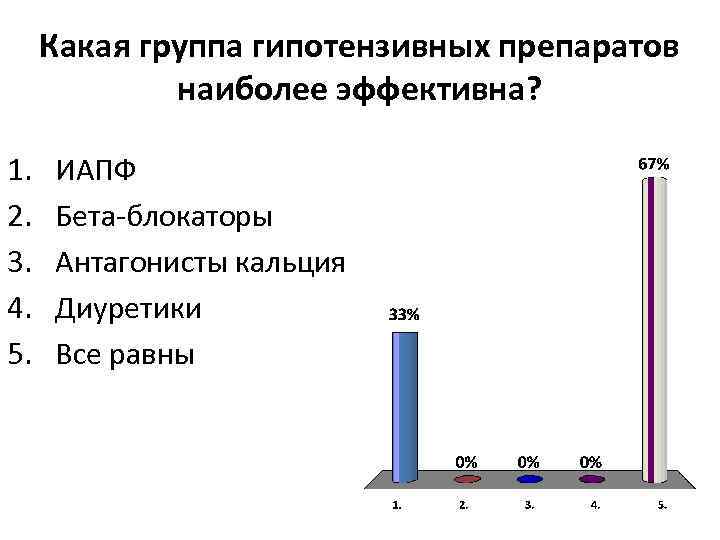

Какая группа гипотензивных препаратов наиболее эффективна? 1. 2. 3. 4. 5. ИАПФ Бета-блокаторы Антагонисты кальция Диуретики Все равны

Какая группа гипотензивных препаратов наиболее эффективна? 1. 2. 3. 4. 5. ИАПФ Бета-блокаторы Антагонисты кальция Диуретики Все равны